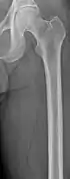

Femur with multiple myeloma lesions

Same femur before myeloma lesions for comparison

The diagnostic examination of a person with suspected multiple myeloma typically includes a skeletal survey. This is a series of X-rays of the skull, axial skeleton, and proximal long bones. Myeloma activity sometimes appears as "lytic lesions" (with local disappearance of normal bone due to resorption) or as "punched-out lesions" on the skull X-ray ("raindrop skull"). Lesions may also be sclerotic, which is seen as radiodense.[70] Overall, the radiodensity of myeloma is between −30 and 120 Hounsfield units (HU).[71] Magnetic resonance imaging is more sensitive than simple X-rays in the detection of lytic lesions, and may supersede a skeletal survey, especially when vertebral disease is suspected. Occasionally, a CT scan is performed to measure the size of soft-tissue plasmacytomas. Nuclear Medicine Bone scans are typically not of any additional value in the workup of people with myeloma (no new bone formation; lytic lesions not well visualized on nuclear bone scan).